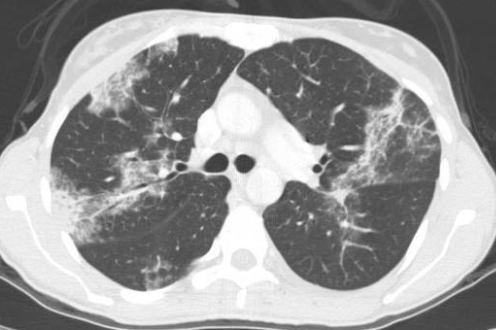

- Pneumonie a Eosinophille

- Plages de verre dépoli bilatérales